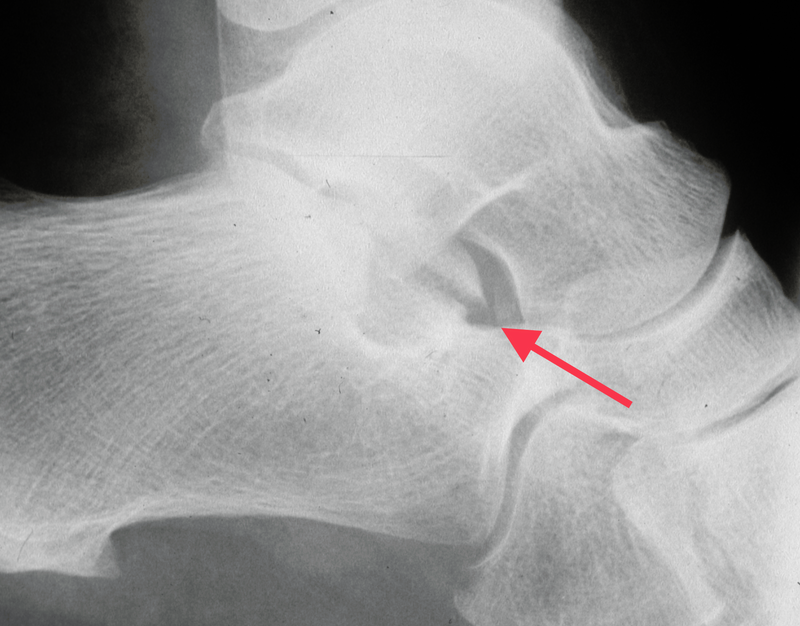

Anterior process of the calcaneum (APC): APC fractures have been considered rare injuries, <3% of extra-articular calcaneal fractures, but the true incidence is probably higher as many of these fractures are missed on initial presentation. It is estimated that up to 40% may be missed on presentation to A&E. The mechanism of injury is thought to be inversion of a plantar flexed ankle which causes the bifurcate ligament attachment to pull off the APC. Because the mechanism is similar they are misdiagnosed as an ankle sprain. These fractures can be classified as type 1 – undisplaced, type 2 – displaced but extra-articular and type 3 – displaced intra-articular. These injuries are often misdiagnosed as sprained ankles as the history will be an inversion injury. Careful examination will reveal tenderness over the APC rather than the lateral ligaments of the ankle but there may be both. AP and lateral X-rays of the ankle may show the fracture on the lateral view, but it can be hard to visualise. A medial oblique view will show the anterior process better. If a fracture is suspected but not confirmed then a CT scan will make the diagnosis and show the extent of the fracture. It may be incidentally picked up on MRI (Figure 4).

Fig 4.jpg

Figure 4: APC fracture involving calcaneo-cuboid joint diagnosed late.

Most of these fractures can be treated non-operatively. Treatment is not standardised but most treatment regimens advocate a period of immobilisation varying from plaster to a boot with protected weight-bearing for up to six weeks. The type 3 fractures involving the joint can be an indication for ORIF if the fragment is large enough. A number of these APC fractures may go on to non-union and cause ongoing symptoms and that becomes a medico-legal problem if the diagnosis has been initially missed. Late treatment is usually excision of the un-united anterior process but patients may still experience ongoing problems and can develop osteoarthritis of the calcaneo-cuboid joint.